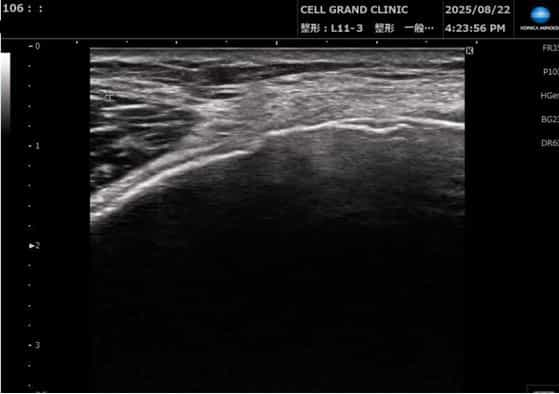

My first ultrasound scan at CELL GRAND CLINIC (Aug 2025). The doctor used this to check the inflammation levels in my left knee before giving me that first exosome injection.